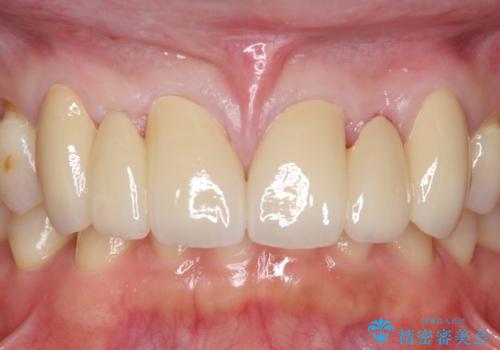

オールセラミッククラウンについて

今回用いたオールセラミッククラウンはジルコニアフレームという白い素材の上にセラミックを盛っているため、審美性が非常に高いのが特徴です。

また、ジルコニアは人工ダイヤモンドの材料にも使われているほど高い強度を持っており、そのためオールセラミッククラウンは審美性だけでなく、奥歯やブリッジの補綴も可能とするクラウンです。